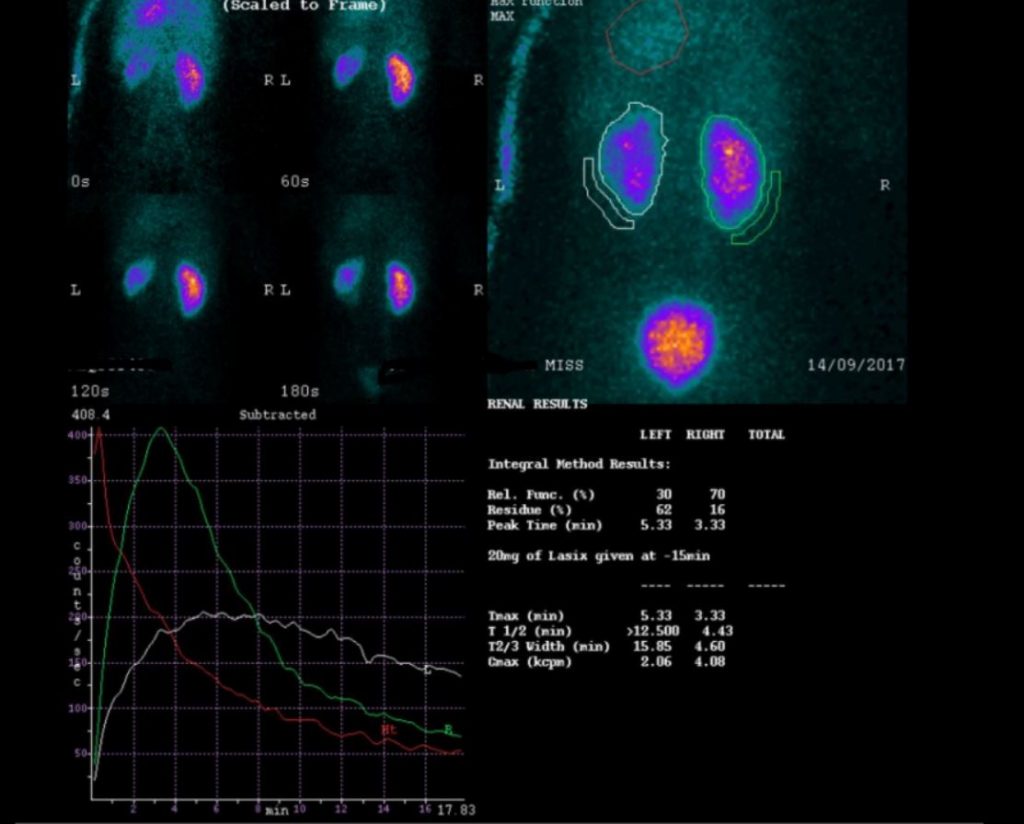

FRCR cases are exam-style radiology cases that simulate the FRCR 2B exam experience. Unlike textbooks, case-based practice allows you to apply knowledge in realistic scenarios, interpreting imaging, forming differential diagnoses, and practising structured reporting.

Understand the FRCR 2B exam format, including short cases & oral exams. Learn what candidates are assessed on & how to prepare effectively.

Preparing for the FRCR 2B exam requires more than reading textbooks or reviewing notes. Success depends on developing structured reporting skills, improving pattern recognition, and becoming confident in exam-style case interpretation.